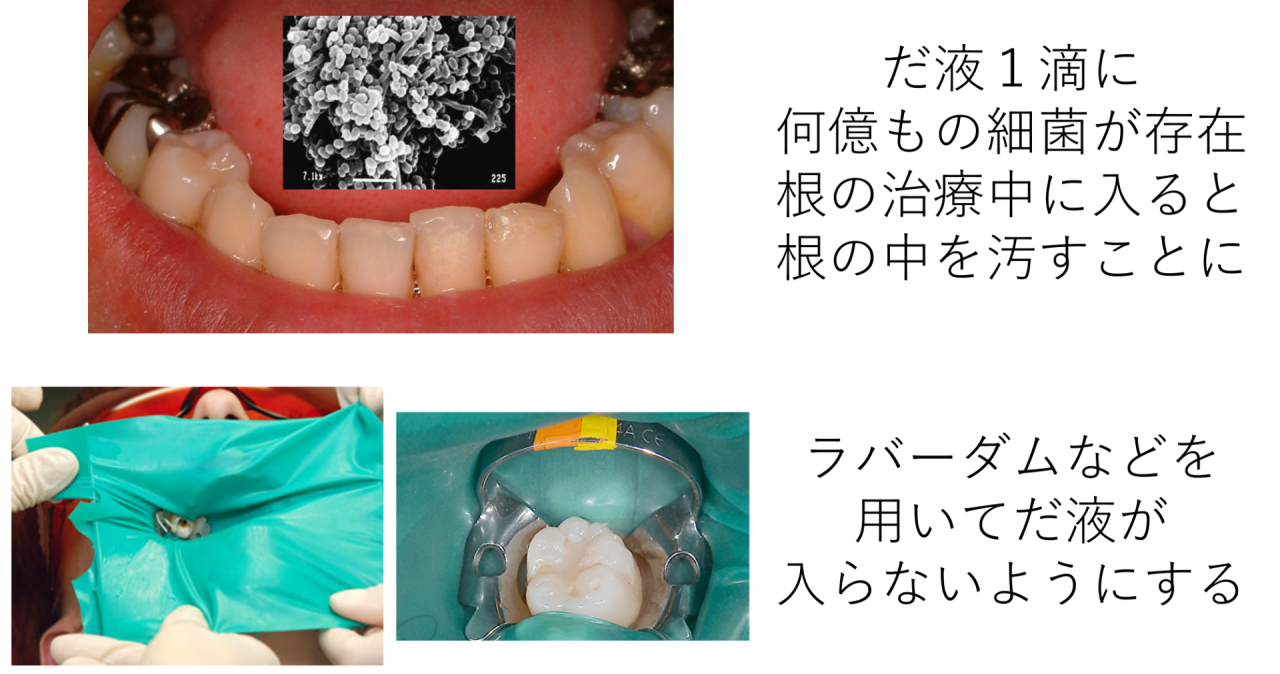

また、下の奥歯はとてもだ液が入りやすい環境です。だ液1滴に何億もの細菌が存在します。これも予想ですが、以前の治療中にだ液が入り、治療をしてきれいにするどころか、反対に根の中に細菌を入れてしまい汚してしまったのだろうと考えました。